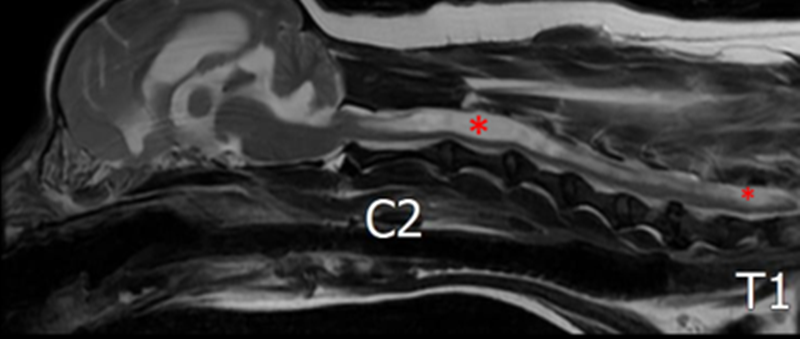

이러한 변화는 CSF 순환 장애를 유발합니다. 그 결과 빨간색 별표로 표시된 것처럼 척수 중심관의 확장이 확인되었고, 뇌에서도 뇌수두증이 동반되어 있었습니다.

척수 중심관의 확장은 경추부터 요추(C2~L3 level)까지 광범위하게 분포하고 있었으며, 특히 C2-3와 L2-3 부위에서 가장 심하게 관찰되었습니다.

경추부터 요추(C2~L3 level)까지 광범위한 척수 중심관 확장이 확인되었으며, 시상 단면상 중심관 확장이 가장 심한 부위는 C2-3 및 L2-3로 평가됩니다.

C2/3 IVDS level에서 확장된 척수 중심관 면적은 43%로 측정되었으며, grade 2(33–60%)로 평가됩니다. ▼

(Severity of SM: grade 0 none, grade 1 <33%, grade 2 33–60%, grade 3 >60%)